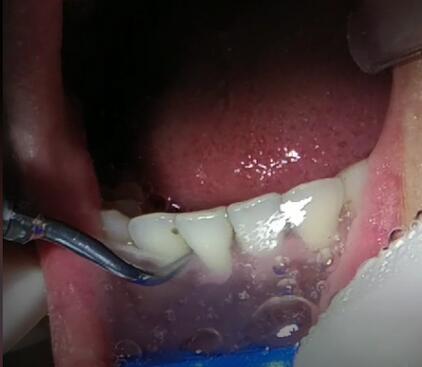

洗牙用的器械不是钻头! 绝不是靠“磨”把这些脏东西磨掉。而是最前方的工作尖能产生微小的震动,这种震动你肉眼看不到。同时器械前端还能“喷水”冲洗。

这些脏东西不是牙齿本身固有的结构,所以工作尖与牙石轻轻接触后,它们就能从牙面上主动脱落下来!

这个大黑点就是清洗下来的牙结石